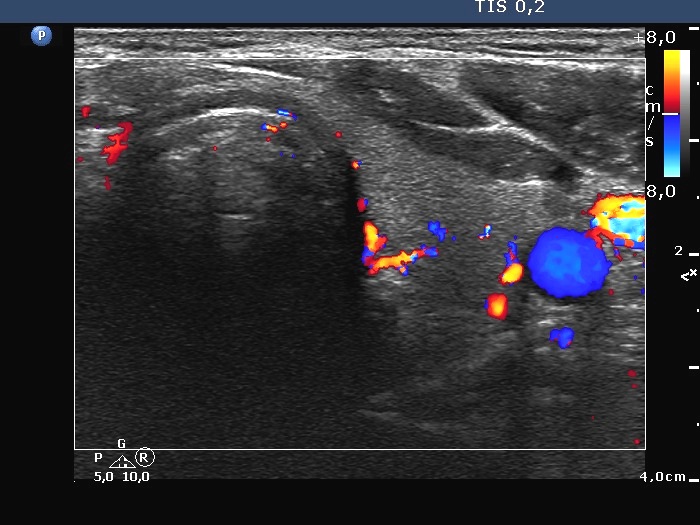

Left lobe, transverse scan, color Doppler mode.